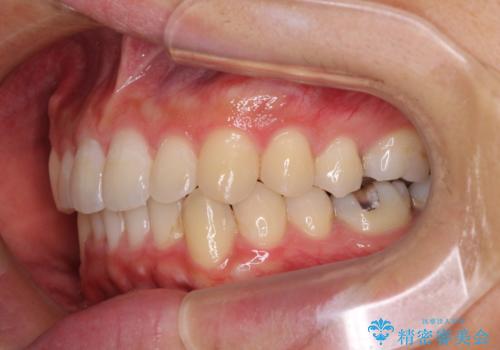

口が少し閉じにくい インビザラインによる非抜歯矯正

- 口元の突出感を治したいとのことで来院された患者様です。

上下顎ともにIPR(歯と歯の間を削る)と歯列全体の拡大によって口元が引っ込むように設計し、インビザラインにより治療を行うこととしました。

抜歯をして口元を下げなければならないほど出っ歯ではなかったため、少しずつ治療ゴールを変更しながら仕上げていきました。

気になっていた前歯の飛び出した印象は、最終的にはスッキリと引っ込み、大変満足していただきました。